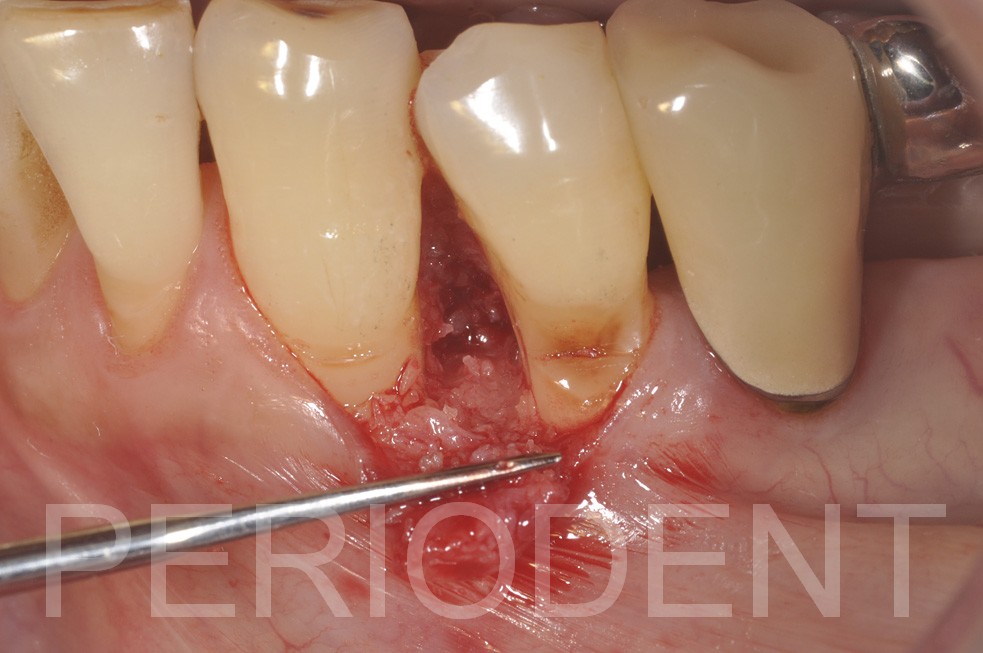

陳柏堅醫師發表左下第一小臼齒近心深度囊袋之牙周再生手術

手術時利用顯微鏡作小範圍翻瓣,清除肉芽組織,牙根整平,塗上

Emdogain

及補骨後縫合